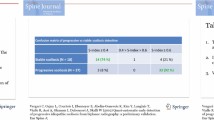

Inter and intra observer reliability among 5 examiners at 4 different intervals were presented in Table 1 for different King’s type each with a minimum of 10 radiographs per group. Table 1 represents the consistency ratio and its corresponding Kappa value for different classification procedures (manual, computer assisted and computerized image understanding). The consistency is very poor in the manual method compared to computer assisted and computerized image understanding. The clinical interpretation of Kappa (κ) values are summarized using bounding values as follows: slight agreement between κ=0.00 and 0.20, fair between κ=0.21 and 0.40, moderate between κ=0.41 and 0.60, substantial between κ=0.61 and 0.80, and almost perfect between κ=0.81 and 1.00.

In the manual classification procedure, each examiner has to remember the classification definition by King and he has to find the required parameters as mentioned in the requirements. It includes the manual calculation of Cobb angle and definition of vertebral end plates. If the examiner fails in defining the vertebral end plates, that error will be propagated to classification procedure. Other indexing parameter also depends on the landmark identification procedure. Landmark identification on radiograph is a tedious process, also varies from person to person and time to time. Hence the consistency is in the moderate range.

The computer assisted method depends on digitized 70 landmarks. The consistency ratio is in the reliable range. Here all the manually identified landmark on digital radiographs needs human intervention, remaining steps follows computer assisted methods. The Kappa statistics for this methodology lies between moderate(<0.6) and substantial range (0.7).

Computerized image understanding system, first extracts the features as required for the computer assisted technique by the examiner. For extraction, image processing technique is used without any human intervention. The required landmarks are automatically (coordinates points for medial axis and CSL coordinates) recorded as its coordinate points. The classification procedure needs number of curves and its deviation at different stages. That is quantified by displacement of the medial axis from its CSL. This will categorize radiographs into different types as per the King’s definition. For the moderate curve range, the consistency ratio and Kappa value both are in good range. As a special case curve with more severity (>50), the defined Gaussian filter in the ROI selection may not work with full accuracy, under such situation one may have to increase the filter range. This increase in the filter range highlights unwanted region as rib cabs and pelvis region. Removal of noise may work up to some extent not of the required level. The Kappa statistics for proposed methodology falls between substantial and perfect range. The proposed system shows better classification consistency compared to manual and computer assisted. Landmark identification in case of manual and computer assisted system are time consuming and it needs expert radiologist. In the proposed research the observer doesn’t require any training in the classification procedure and manual landmarking is completely avoided. Still there is some consistency deficiency due to presence of noise in the radiographs. During the extraction of the vertebral column due to noisy nature of X-ray, one may have to select higher value for the Gaussian filter. This higher value leads to more extraneous information in the selected ROI. This minor error may cause misclassification, but works well compared to existing system.